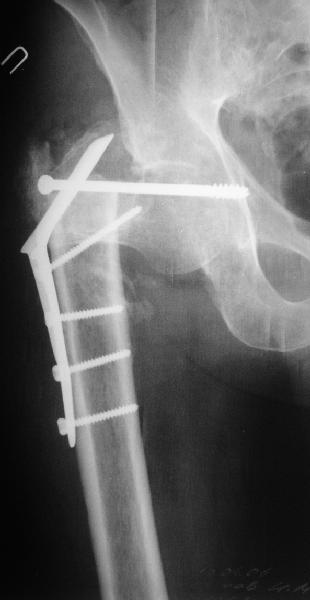

В приложении пример пациента, близкого по картине к тому, что

представил Виктор (варус и смещение периферического отломка на

поперечник кзади). Сделали как раз то, что Виктор исходно намеревался

- аппаратная коррекция и затем гамма.